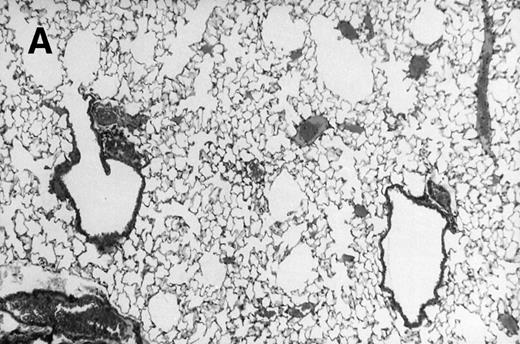

Allogeneic transplanted mice (B10.BR → CBA) with GVHD and, as controls, allogeneic transplanted mice without GVHD and syngeneic transplanted mice (B10.BR → B10.BR) were infected intranasally with HSV-1 at 12 weeks after transplantation. As an additional control, age-matched normal CBA mice were infected as well. Histological examination of lungs was performed in mock-infected mice and in mice at day 7 after infection. Allogeneic transplant recipients with GVHD showed increased pathology (Fig 1). Scores reflecting the periluminal histopathologic changes were significantly higher (P = .05; Student's t-test) in allogeneic transplant recipients with GVHD, when compared with control mice (Fig 2). The periluminal histopathologic scores were also higher in allogeneic transplant recipients with GVHD, when compared with normal CBA mice, at days 4, 10, and 14 after infection (data not shown). No significant differences were observed in the scores reflecting the parenchymal histopathologic changes (data not shown). Because the results in syngeneic transplanted mice were very similar to those in allogeneic transplanted mice without GVHD, the latter, which are the most appropriate control for procedural effects and for the effect of GVHD, and normal CBA mice, were used as controls in further experiments.

Allogeneic transplant recipients with GVHD showed increased pathology. Photomicrographs of lung sections stained with hematoxylin and eosin show evidence of increased pathology in infected allogeneic GVHD mice. (A) Normal CBA, mock-infected, original magnification × 25; (B) normal CBA, mock-infected, original magnification × 100; (C) normal CBA, infected, original magnification × 40; (D) normal CBA, infected, original magnification × 100; (E) allogeneic GVHD, mock-infected, original magnification × 10; (F) allogeneic GVHD, mock-infected, original magnification × 75; (G) allogeneic GVHD, infected, original magnification × 10; (H) allogeneic GVHD, infected, original magnification × 100.